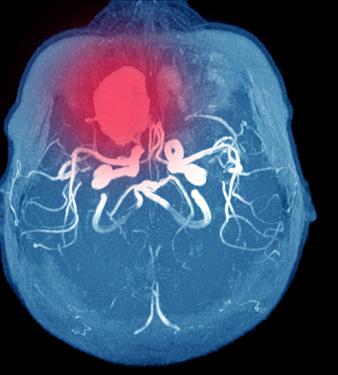

Bilde 2: MCA (a. cerebri media) bifurkasjonsaneurisme (sitter i delingen av et kar). Her 3-dimensjonalt fremstilt fra CTA (CT-angiografi) som gir god oversikt over hvor inngående og avgående grener fra aneurismet (M1 = hovedstamme av a. cerebri media, M2 = første større forgreining av MCA, A1 = hovedstamme av a. cerebri anterior)